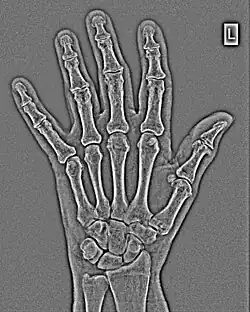

The conventional way of interpreting radiographic images in medicine is to regard them as representations of human anatomy. In the mathematical analysis of these images, however, we can interpret them as fluctuations of signal amplitude in space, as demonstrated in Figure 1.23.

FFTs can also be calculated in two-dimensions to give results such as those in Figure 1.27. Since Fourier analysis generates results in terms of both positive and negative spatial frequencies, these can be plotted in the form of a 2D image so that the maximum frequency lies at the origin and those for the horizontal and vertical directions are shown increasing towards that origin. The modulation at different spatial frequencies is represented using a grey-scale. Low frequency bands can be seen along the horizontal axis in the figure, for example, representing the horizontal periodicity of image data from the fingers, while finer bands along the y-dimension are indicative of a periodicity of image data from the various metacarpophalangeal joints. Higher frequency features can also be seen running diagonally in this 2D-FFT, representative of the trabecular structure of the bones, for example.

The essence of this approach is that it can be used to produce a range of image processing effects by enhancing and/or suppressing features in the 2D-FFT and then converting the result back into the spatial domain using the IFT, as illustrated in Figure 1.28. Such image manipulations are considered in more detail in a later chapter. Note that the form of image processing demonstrated in the figure is for purely illustrative purposes and bears no direct medical significance.